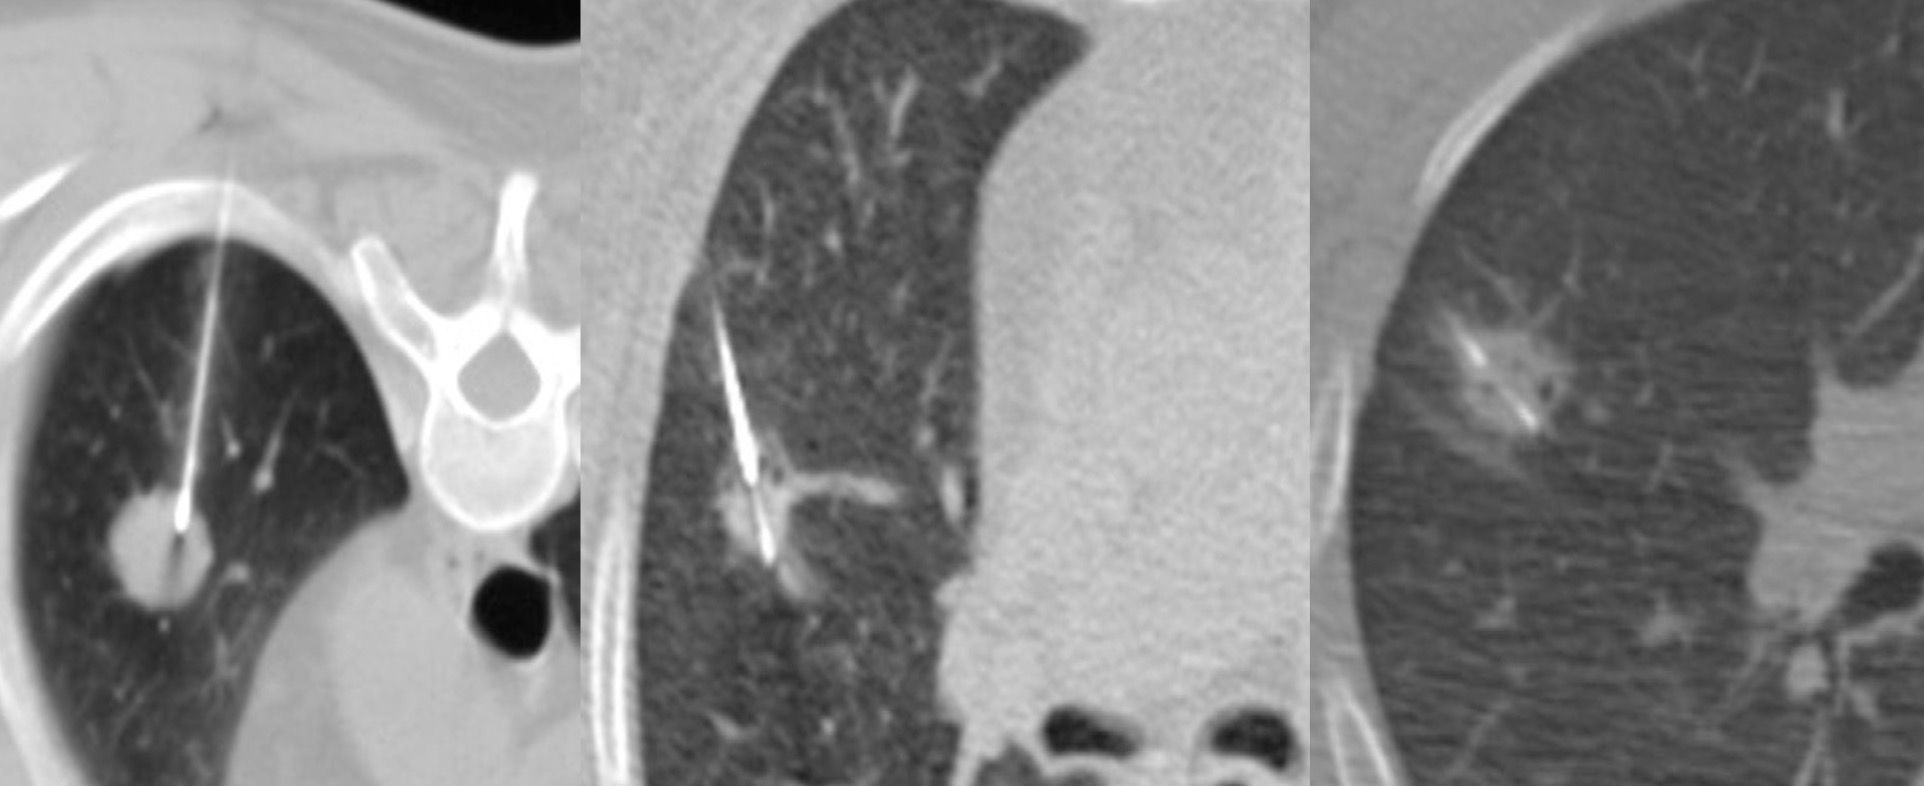

A 70-years old treated in the past for carcinoma breast was found to have a new, sclerotic left 5th rib lesion on PET, confirmed on MRI. She was refused a biopsy because of the risk of lung injury.

She came for an opinion and we agreed to do a biopsy.

Please click on the Subscribe button below to see the video describing the case, the technique, the pitfalls, similar other cases as well as the concept of railroading used in this case.